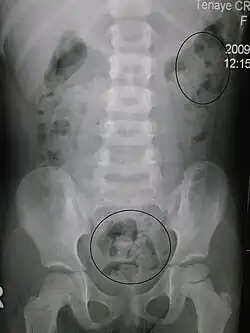

| Constipation in a young child seen on X-ray. Circles represent areas of fecal matter (stool is white surrounded by black bowel gas). | |

Abdominal X-rays are generally only performed if bowel obstruction is suspected, may reveal extensive impacted fecal matter in the colon, and may confirm or rule out other causes of similar symptoms.[26][17]